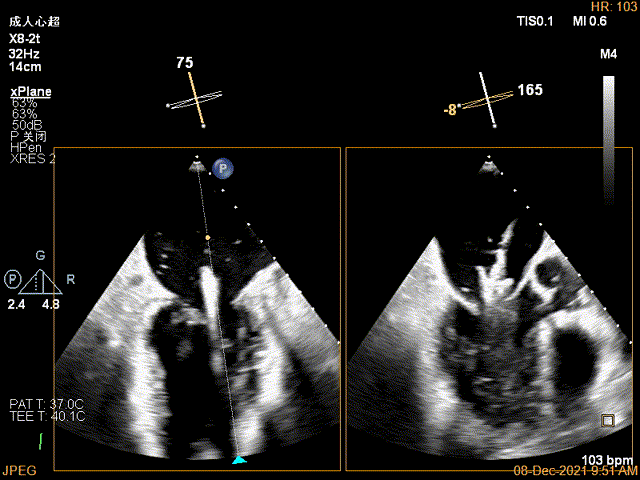

X-plane:下夹子尝试先捕获2区瓣叶

夹子关闭过程中,Color提示2区反流逐渐减少,残余反流位于夹子外侧

x-plane验证前后叶抓捕后bond明显

3D-VIEW验证结果